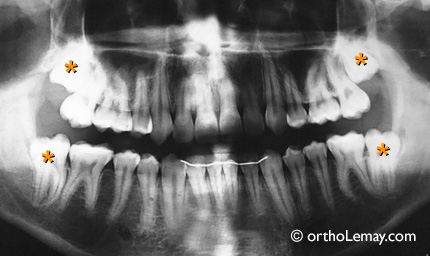

Sous toutes réserves, de telles molaires peuvent probablement être corrigées orthodontiquement et « sauvées » comme illustré dans l’exemple ci-dessous où des deuxièmes molaires semi-incluses ont été redressées au lieu d’être extraites.

Le redressement de molaires peut être indiqué même s’il n’y a pas eu de perte de dents comme chez cet adolescent où les deuxièmes molaires sont basculées vers l’avant et ne peuvent sortir convenablement. Garder ces dents ainsi les condamne à moyen terme car il est impossible de les nettoyer et elles carieront éventuellement.

Vos deuxièmes molaires (indiquées par un astérisque orange) inférieures sont semi-incluses et vous ne pourrez jamais les brosser ou les nettoyer adéquatement pendant des années. Elles doivent être considérées comme des dents de sagesse car c’est ainsi qu’elles se comporteront et vous affecteront. Ce n’est qu’une question de temps avant qu’elles vous causent d’autres problèmes et elles représentent des « bombes à retardement »!

Vos autres dents semblent en effet assez bien alignées (en se fiant à la radiographie panoramique seulement) et je suis d’accord qu’il serait peu logique d’extraire 2 prémolaires inférieures pour « sauver » les 37 et 47. Avec la seule information que vous m’avez donnée, et sous toutes réserves, il n’y a aucun doute que si vous étiez une de nos patientes je vous recommanderais de faire extraire ces deuxièmes molaires. Si vous extrayez celles du bas, celles du haut sont aussi « condamnées » même si elles sortent car elles n’auront pas de dents antagonistes pour s’appuyer dessus.

À noter que cela ne changera absolument rien à votre fonction car ces 4 molaires sont présentement complètement inutiles. De plus, cela vous soulagera et vous fera économiser beaucoup d’argent!